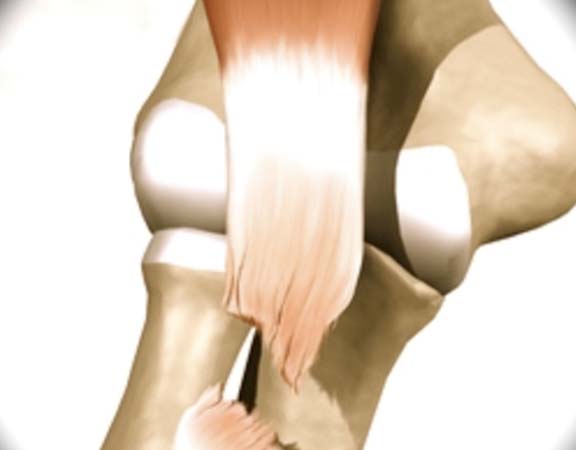

LESÃO DO BICEPS DISTAL

A LESÃO DO BICEPS DISTAL CONSTITUI-SE NA RUPTURA DO TENDÃO AO NIVEL DO COVELO. Acomete homens ao redor dos 30-50 anos, durante o movimento de flexão do cotovelo ao realizar o levantamento de algum peso. É comum sentir um estalo no momento da lesão evoluindo com perda de força. Existem diversos fatores de risco como tabagismo, uso de anabolizantes e doenças sistêmicas como o Lúpus. Ao exame físico apresenta dor na região anterior do cotovelo com inchaço e pode ficar roxo o local. Na maioria das vezes é possível observar uma deformidade em relação ao lado contra-lateral (encurtamento do tendão). O tratamento de escolha é cirúrgico para as lesões totais ou maiores que 50% do tendão. O tratamento conservador é de exceção, somente se o paciente for sedentário e de baixa demanda, pois se não tratado geralmente resulta em perda de força de supinação (±40%), de flexão (±30%) e a resistência.